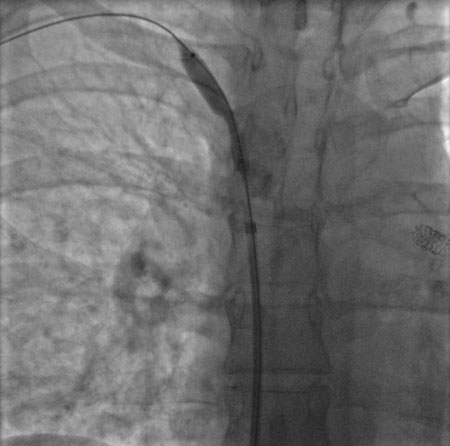

Done percutaneously by obtaining access usually through the femoral vein. Performed under conscious sedation. Fluoroscopic guidance and iodinated contrast are used. Most operators use heparin during the procedure. [Figure caption and citation for the preceding image starts]: Postdilatation of the superior vena cava stentImage obtained from cardiac catheterization laboratory at University of Missouri, Columbia; used with permission [Citation ends].[Figure caption and citation for the preceding image starts]: Venography showing superior vena cava stenosis. Stent placement in the left pulmonary artery is seenImage obtained from cardiac catheterization laboratory at University of Missouri, Columbia; used with permission [Citation ends].

[Figure caption and citation for the preceding image starts]: Stent deployment in the superior vena cavaImage obtained from cardiac catheterization laboratory at University of Missouri, Columbia; used with permission [Citation ends].

Undertaken percutaneously by obtaining access (usually) through the femoral vein. Performed under conscious sedation. Fluoroscopic guidance and iodinated contrast are used and most operators use heparin during the procedure.[Figure caption and citation for the preceding image starts]: Postdilatation of the superior vena cava stentImage obtained from cardiac catheterization laboratory at University of Missouri, Columbia; used with permission [Citation ends].[Figure caption and citation for the preceding image starts]: Venography showing superior vena cava stenosis. Stent placement in the left pulmonary artery is seenImage obtained from cardiac catheterization laboratory at University of Missouri, Columbia; used with permission [Citation ends].